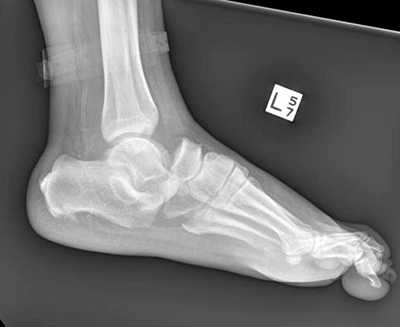

Рентгенологическое исследование

Для диагностики повреждения сустава Шопара делают рентген, КТ и МРТ. На передне-задней рентгенограмме определяют величину пяточно-кубовидного угла. Проводят одну касательную к наружному краю кубовидной кости и вторую касательную к наружному краю пяточной кости. В норме угол между касательными колеблется в пределах от 0 до 5°. Увеличение угла свидетельствует о нарушении стабильности пяточно-кубовидного сочленения. КТ во фронтальной и сагиттальной плоскостях позволяет выявить дефект суставных фасеток, смещение костей при вывихе и фрагментацию костей при переломе. КТ, по сравнению с рентгенографией, является более информативным методом диагностики. МРТ позволяет выявить дефекты отдельных связок.

Рис. 9. Переломо-вывих в суставе Шопара

При рентгенографии все снимки выполняются в сравнении со здоровой стопой. Существует несколько основных рентгенологических признаков повреждения сустава Лисфранка. 1. Отсутствие параллельности медиального края основания 2-й плюсневой и медиального края медиальной клиновидной кости 2. Расширение между основаниями 1 и 2 плюсневых костей 3. Наличие костного фрагмента в области основания 2-1 плюсневой кости 4. Тыльный подвывих на боковой проекции 5. Разрыв линии предплюсне-плюсневого сочленения.

У нашей пациентки произошёл гомолатеральный вывих, то есть все плюсневые кости сместились в наружном направлении. На стандартных рентгенограммах в свежих случаях данные повреждения пропускают практически в 100% случаев. Необходимо делать рентгенограммы обеих стоп стоя с нагрузкой весом тела и даже в такой ситуации неопытный глаз пропустит травму.